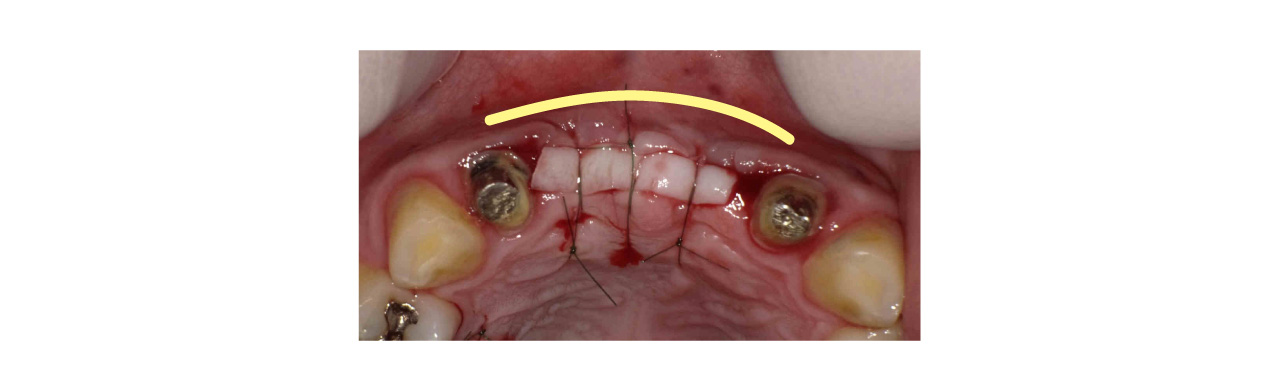

歯茎を詰めたのちに縫合を行います。歯茎を詰めたことにより頬側の歯肉が厚みを増して膨らんでいます。

頬側に折り込まれたことにより頬側の歯肉が厚みを増して膨らんでいるいます。

以上のように、インプラント周りに骨を作ることは骨の中にインプラントが埋入されないといけないので当然必要です。それに加えて分厚い歯茎を作らないと作った骨も吸収してしまいインプラントが長く生存できないのです。インプラントは歯が入って終わりではなく、長持ちしないといけません。分厚い歯茎を作ることは見落とされがちですが、とても重要な手段になります。